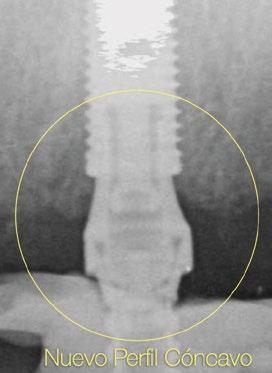

Innovaciones y características del nuevo pilar Multi-unit: perfiles para preservar Debido a esta compleja situación, se ha desarrollado una nueva línea de pilares Multi-unit que rompe con los diseños clásicos y que se presenta a continuación: (Figs. 4,5).

Con respecto al Multi-unit recto, su principal característica es la emergencia desde la plataforma del implante con un perfil completamente cóncavo. Por una parte, va a maximizar el efecto de “cambio de plataforma” en su parte más crestal a nivel de la plataforma del implante y por otra va a facilitar mucho más espacio para la creación de tejido conectivo supracrestal a lo largo de toda la transición hasta la plataforma restauradora. El perfil cóncavo del pilar también respetará en mayor medida los espacios comprendidos entre el pilar y el hueso interproximal (en el caso de una colocación subcrestal entre 1,5 y 2mm) para poder preservar al máximo las estructuras anatómicas presentes que soportarán las papilas periimplantarias.

Así como el diseño clásico de pilar hacía prácticamente imposible la colocación de implantes inmediatos en zona estética, el nuevo perfil cóncavo del pilar Multi-unit hace que se convierta en un pilar ideal para estas situaciones. La altura de pilar de 3 ,5 mm, hace que se pueda colocar la plataforma del implante en la posición corono-apical deseada con respecto al margen gingival sin involucrar el hueso adyacente y permitiendo desarrollar un mínimo perfil de emergencia restaurador más horizontal para soportar cenit y tejido interproximal. (Fig.6-7) Otra característica de diseño importante es la reducción del bisel de la plataforma res-

tauradora tanto en los pilares rectos como en los pilares angulados. Sin cambiar su diámetro clásico de 4,8mm ni su compatibilidad para atornillar y asentar cualquier aditamento restaurador de toda la gama Multi-unit, el nuevo pilar presenta una plataforma mucho más fina y estilizada que facilitará también su inserción incluso sin necesidad de utilizar la fresa “bone mill” o molinillo de hueso. De esta manera no solo se seguirá incrementando la preservación ósea, sino que también se reducirán los tiempos quirúrgicos al evitar tener que atornillar y desatornillar la guía del molinillo o “Bone Mill Guide”. (Figs. 8-12)

Sin duda, los perfiles mejorados del Multi-unit recto aportan beneficios claros e inmediatos que facilitarán la práctica clínica, pero el pilar que realmente revoluciona e innova es el nuevo pilar angulado. (Fig.13)

En esta ocasión se ha logrado reducir el tamaño del robusto pilar original a la mínima expresión, obteniendo líneas suaves, finas y redondas. De nuevo, esta forma comulga mucho más con los conceptos mencionados anteriormente. Además, proporcionará un verdadero impacto en la manera de planificar y en los resultados a largo plazo. Seguidamente se describen algunos ejemplos clínicos para las angulaciones de 30º y 17º respectivamente:

radiografías periapicales comparativas a los 3 meses de la colocación como el implante en posición #1.2 tiene signos de remodelación fisiológica. Hecho que no ocurre en los pilares con nuevos perfiles al ofrecer transiciones más suaves que respetan los principios biológicos.

Los nuevos diseños de perfiles cóncavos de los pilares Multi-unit han llegado al mercado para quedarse. En esta publicación se han descrito detalladamente las limitaciones de los pilares actuales con respecto a las necesidades modernas en implantología. A pesar de carecer de evidencia científica sólida y experiencia clínica a largo plazo, los conceptos básicos sobre diseño de perfiles de emergencia en implantes unitarios y estética periimplantaria se han aplicado al diseño de los nuevos pilares Multi-unit para respetar y preservar las estructuras anatómicas periimplantarias, aportando los beneficios para los profesionales y provocando un impacto real en el mantenimiento de la salud oral de los pacientes.